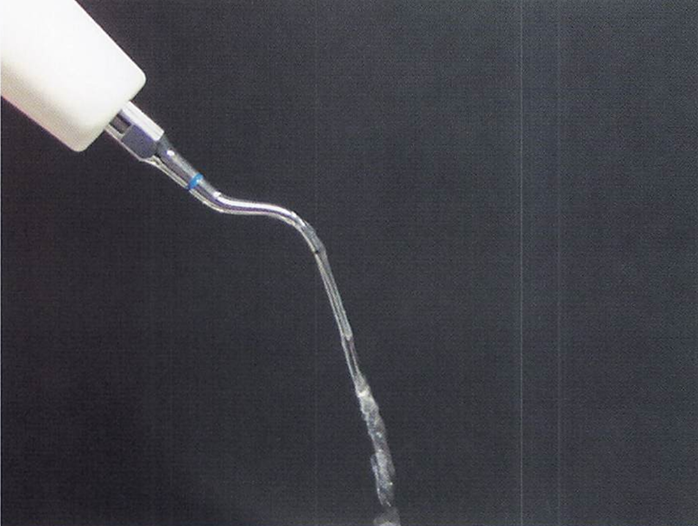

午前-70

超音波スケーラーのチップと水流の写真を別に示す。 使用法で正しいのはどれか。2つ選べ。

a. 術前に口腔外で水流の確認を行う。

b.チップの先端をポケット底部まで挿入する。

c.チップは30度で歯に当てる。

d.50gの側方圧をかける。

解答を見る

a.b